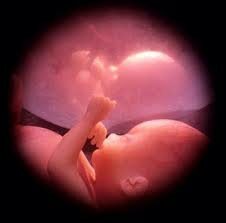

• Se chupa el dedo, toca su cara (Semana 20)

Se chupa el dedo, toca su cara (Semana 20)

Sus movimientos son más rápidos, mide acerca de 25 cms. desde la cabeza hasta los dedos de los pies, el líquido que traga le ayuda a que su sistema digestivo funcione